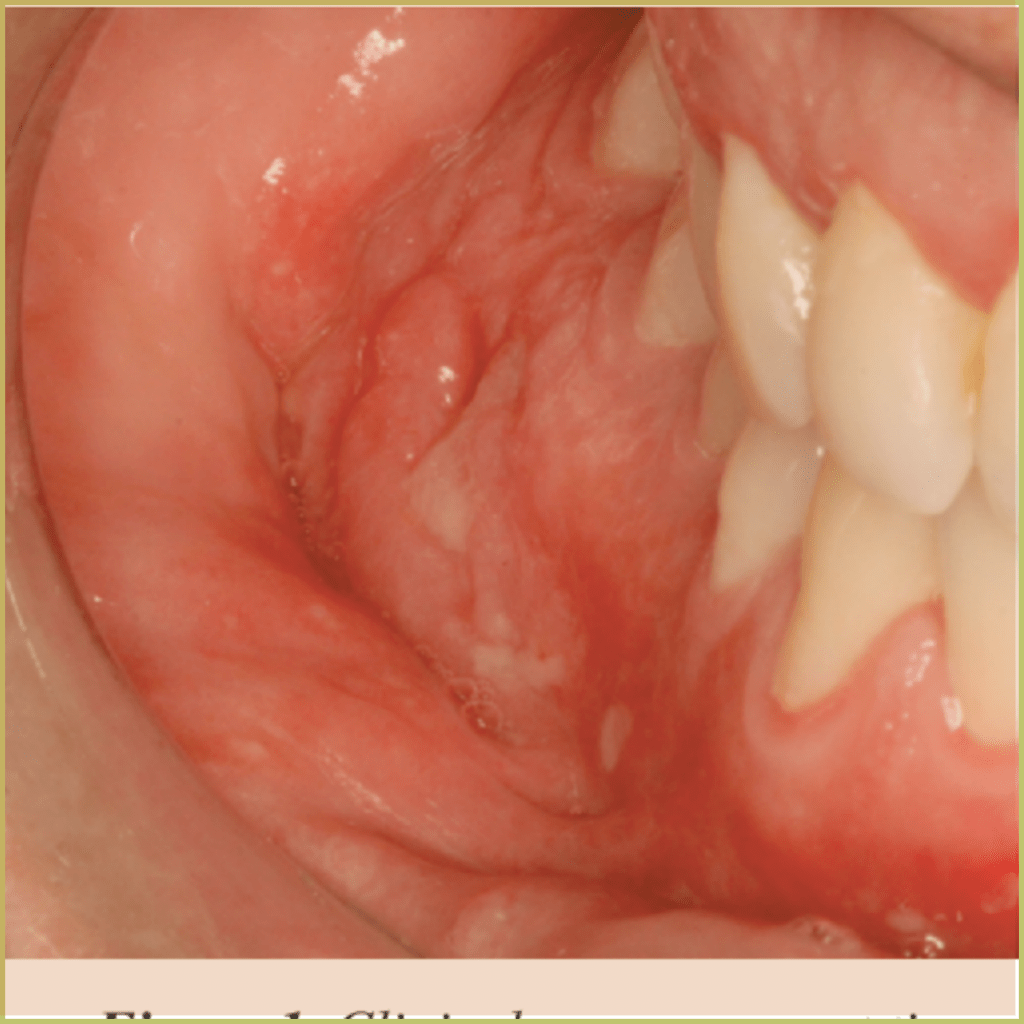

SQUAMOUS CELL CARCINOMA

Squamous Cell Carcinoma (epidermoid carcinoma) is the most common head and neck malignancy. The tongue is the most common subsite and is associated with higher mortality when compared to other affected areas. Risk factors include tobacco-derived carcinogens, excessive alcohol consumption, and possibly exposure to human papillomavirus (HPV 16 and 18). The common clinical presentation includes:

- Early lesion – white or red-white macule (leukoplakia, erythroplakia).

- Mature lesion – ulceration, induration, elevated margins.

- Advanced lesion – may impede function/movement or erode adjacent bone.

- Most likely found on the lateral surface of the tongue, floor of the mouth, and lower lip vermilion.

- Trismus or cervical lymphadenopathy may indicate metastases.

Diagnosis is based on the lesion history, clinical presentation and microscopic findings, which may include:

- Invasive islands and cords of epithelial cells.

- Nuclear pleomorphism with large nuclei (increased nuclear to-cytoplasmic ratio).

- Dyskeratosis.

- Architectural disorganization of proliferating cells.

Your differential diagnosis should include:

- Chronic traumatic ulcer.

- Primary syphilis.

- Actinic keratosis.

- Keratoacanthoma.

- Wart.

- Another neoplasm (basal cell carcinoma or melanoma).

Treatment options include:

- Surgical excision.

- Combined surgery and radiation therapy.

- Chemotherapy.